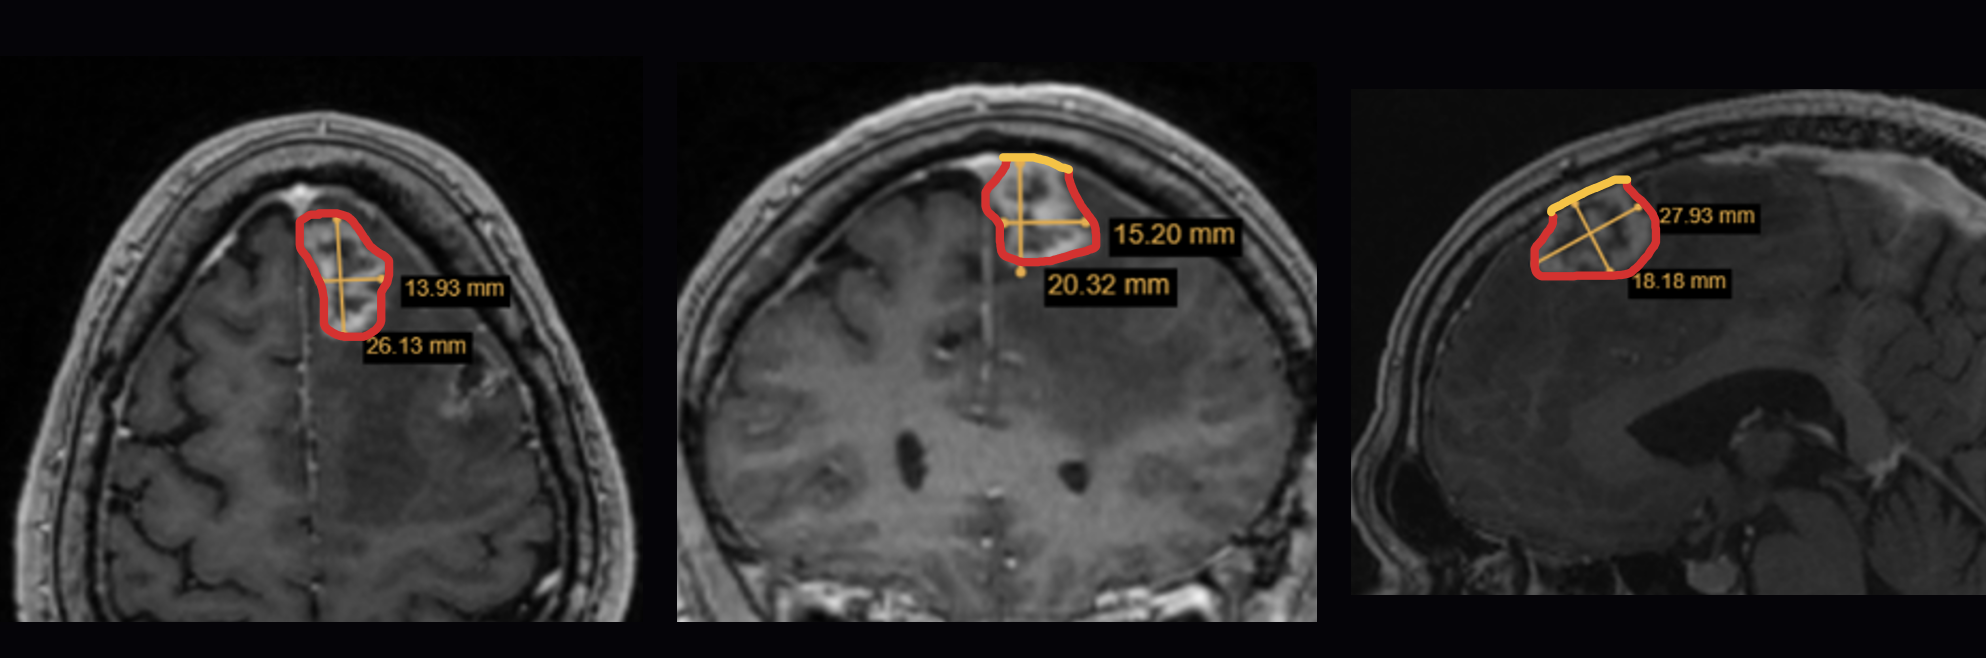

Tool for estimation of at-risk post operative tumor bed surface area

The Brain Resection Cavity Estimation Tool is intended to assist with tumor bed calculations, based on relevant patient data, for patients undergoing tumor resection surgery with GammaTile.